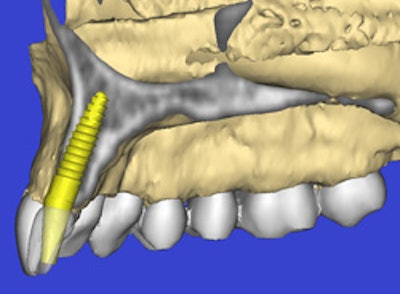

"One reason to do planning with 3D is to relate the implant to critical anatomical structures such as the mandibular canal, which contains nerve bundles that provide sensation to the lower lip," he said. "If impaired, a patient can have a loss of sensation in the lip, they can drool, and they will have reduced quality of life."

| Integrated implant treatment planning systems such as the iCATVision can improve outcomes, encourage patient acceptance, and reduce treatment times. |

Cone-beam CT image data and surgical guides can also be integrated with in-office CAD/CAM systems such as the Cerec or E4D, Dr. Tyndall added, enabling dentists to diagnose, treatment plan, design, and fabricate all in the dental office. In fact, the vendor community has been one of the drivers behind the growing adoption of cone-beam CT in dentistry, Dr. Ganz noted.